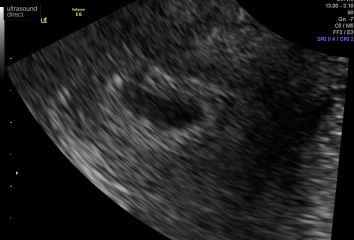

Hey all, looking for some reassurance/positive stories. I had a early viability scan today as I thought we were 7w1d. Went and we were measuring 5 and a half - 6 weeks with no fetal pole or yolk sac seen, though gestational sac was there.

Thank you . It was external and internal. Due to my high bmi they struggled to see external and internal was alot clearer which showed empty gestational sac x